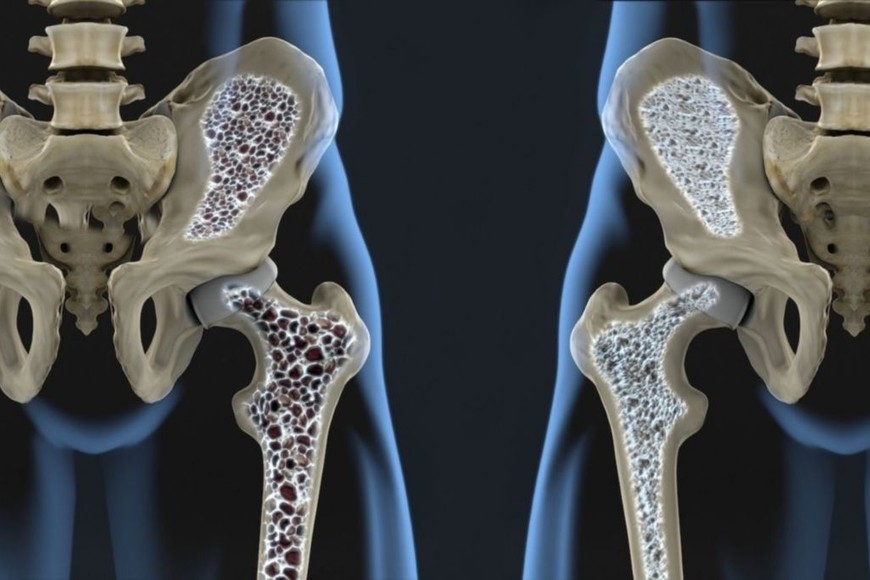

La osteoporosis es una enfermedad del esqueleto, en la que se produce una disminución de la densidad de la masa ósea total. Esto es fragilidad y porosidad en aumento en los huesos que producen fracturas ante los mínimos traumas. A veces, son espontáneas.

Es una afección generalizada y silenciosa que hace que los huesos sean débiles y frágiles. No tiene síntomas visibles, por lo que muchas personas no saben que la tienen.

“La fractura se produce debido a la fragilidad que presenta la estructura ósea ante un mínimo trauma, como ser la caída desde su propia altura, y esto depende de varios factores: el contenido mineral del hueso (que se evalúa mediante la densitometría), la geometría del hueso, la microarquitectura (disposición tridimensional de la trama ósea) y la calidad de los componentes del hueso, así como del mecanismo e intensidad del impacto”, comentó Andrés Ferrero (M.N.: 118.271), coordinador del Programa de Osteoporosis del Hospital de Clínicas.